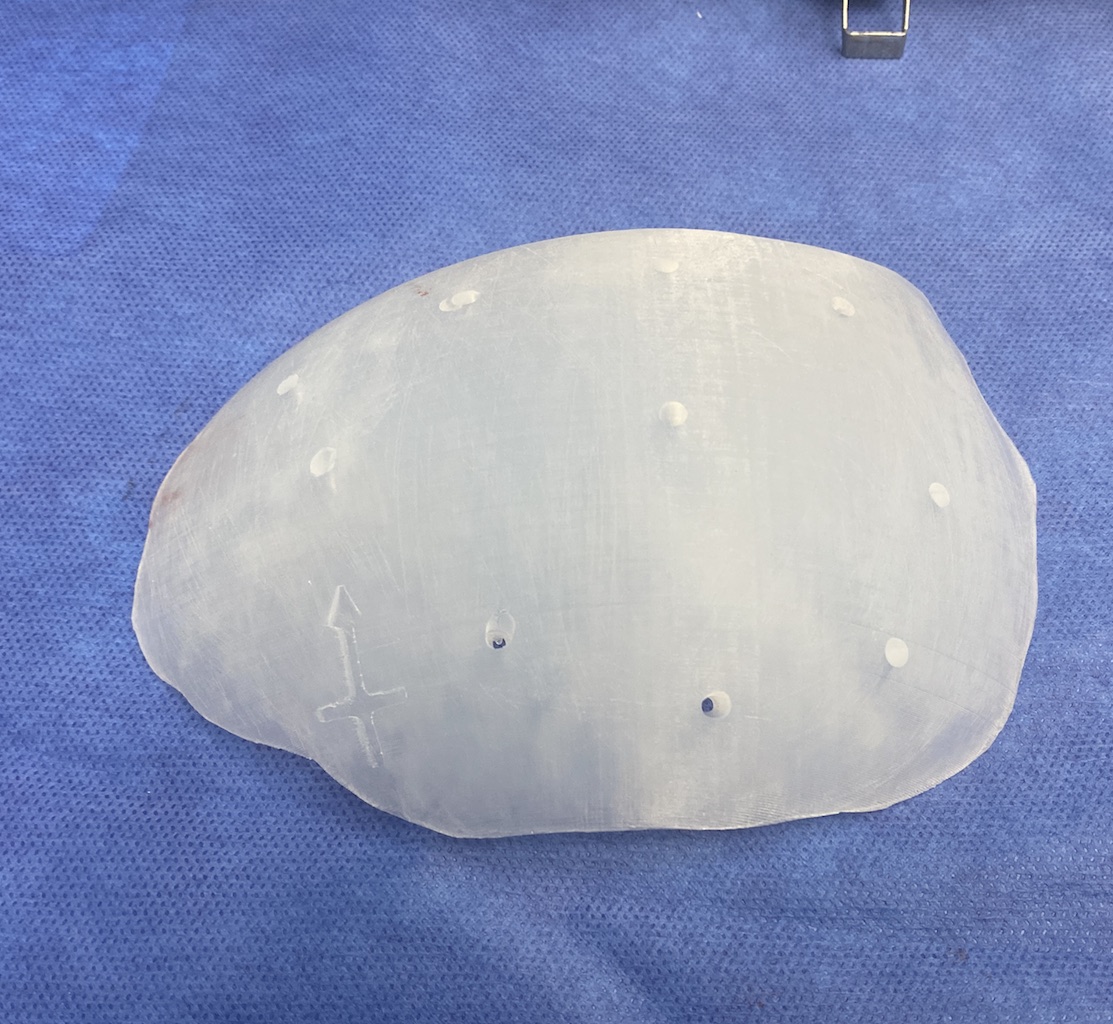

Patient 28

Desire for rounder shape to the top of the head from a congenital parasagittal deficiency skull shape.

Custom skull implant designed to fill in the parasagittal deficiencies.

Desire for rounder shape to the top of the head from a congenital parasagittal deficiency skull shape.

Custom skull implant designed to fill in the parasagittal deficiencies.